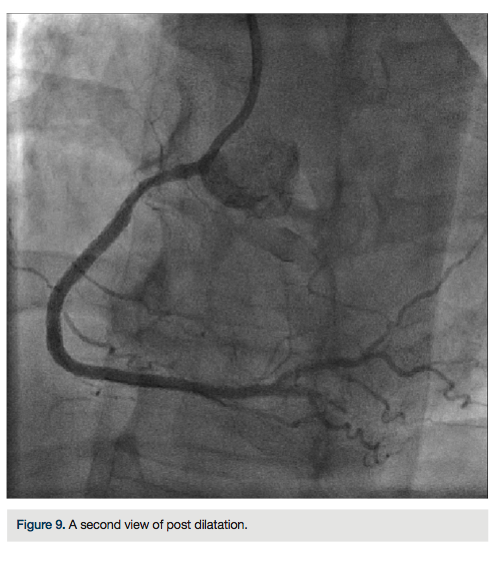

There was transient loss of flow in the posterior left ventricular branch (PLV), which was wired with a Fielder XT wire, and then changed out for a Pilot wire through an over-the-wire balloon (Figure 7). We exchanged for a Runthrough wire into the distal posterior descending coronary artery (PDA). The Corsair was removed from the collateral, and we took the guide and wire from the left system. Two additional 3.0 x 28 mm Promus drug-eluting stents were placed distally prior to the bifurcation. After stent placement, there was good flow in the distal vessel. A gap in between the stents was covered with a 3.0 x 8 mm Promus drug-eluting stent. We then

post dilated with a 3.25 x 15 mm Quantum balloon (Boston Scientific) at high pressure (Figures 8-9). Because of a pseudo lesion in the proximal vessel, we exchanged out for a Judkins right (JR) 4 guide and gave 200 mcg intracoronary (IC) nitroglycerin. Angiography revealed TIMI-3 flow in the vessel without any perforation or embolization (Figure 10). The patient tolerated the procedure well. The guide was removed and a TR Band (Terumo) was placed over bilateral radials. The patient has done well clinically, and is approximately 6 months post PCI with excellent functional capacity and no ischemic symptoms.